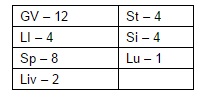

Исцеляющие точки нашего организма.

подробный атлас

АКУПУНКТУРНЫЕ ТОЧКИ

АКУПУНКТУРНЫЕ ТОЧКИ